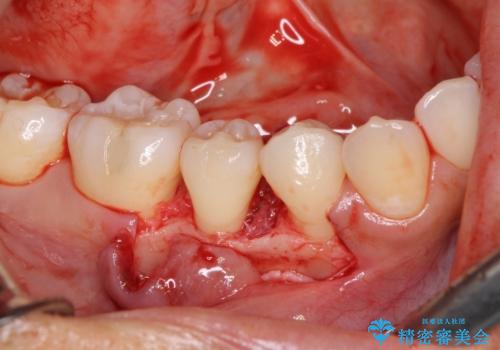

患者様は、他院で右下の歯を抜歯かもと言われました。全体の歯周病はなく、右下の1歯だけ骨が極端に減少していました(初診時歯周ポケット7mm。通常は3mm以下。)。その歯だけ咬合が強いことが原因と考えられたため、咬合を弱くする処置と減少した骨を再生する処置が必要になりました。

骨の再生治療手術をして10か月経過観察をしたのち、骨を平坦化する手術を行い、治療終了となりました。

・再生治療は、局所的な骨の減少が対象となります。

・ほとんどの場合、2回目の手術(骨を平坦化する等)が必要になります。